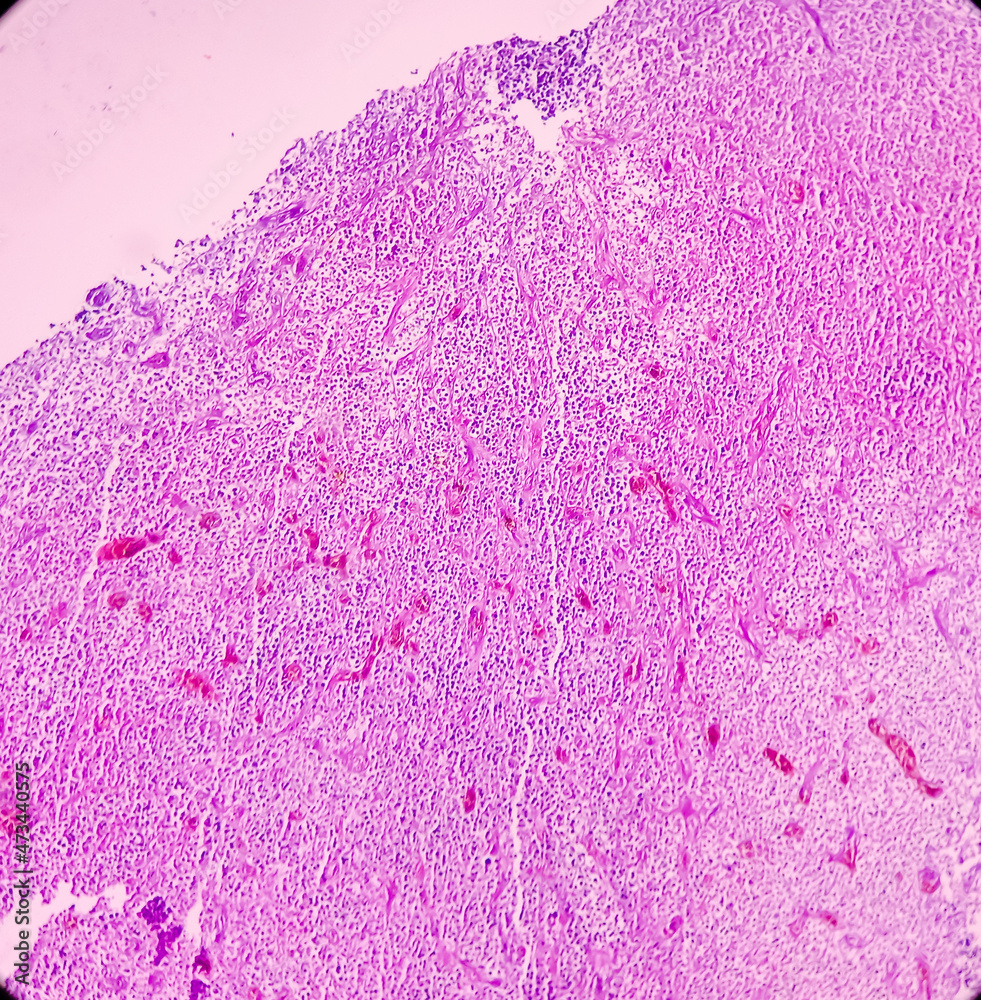

Histopathological examination of the patient's malignant neoplasm, with Malignant Neoplasm Neck Learn about nasopharyngeal (upper throat), oropharyngeal (middle throat) cancer, hypopharyngeal (lower throat) cancers, and more. head and neck cancers include cancers that start in the mouth, throat, sinuses and salivary glands. head and neck cancers can have many different names depending on where the cancer starts. head and neck cancer starts when a normal cell turns malignant. Malignant Neoplasm Neck.

A Histopathological evaluation showing a malignant neoplasm with Malignant Neoplasm Neck metastatic squamous neck cancer with occult primary is a disease in which squamous cell cancer spreads to lymph nodes in the neck and it. Learn about nasopharyngeal (upper throat), oropharyngeal (middle throat) cancer, hypopharyngeal (lower throat) cancers, and more. head and neck cancers can have many different names depending on where the cancer starts. head and neck. Malignant Neoplasm Neck.